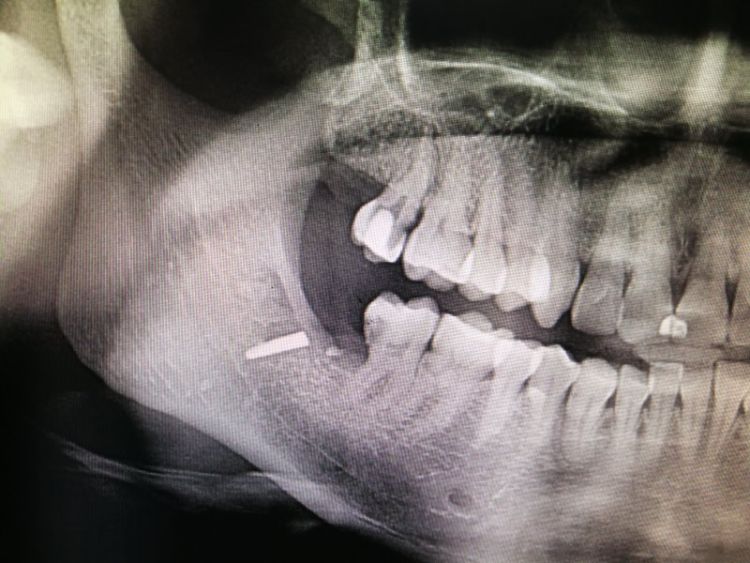

李女士口腔内的金属物。这一检查,把她吓了一跳。据其在松岗人民医院口腔科拍摄的x光片显示:她之前拔掉的智齿牙窝里,残留了两节金属物,并且已经没入很深,快要接近下颌神经管了。如果再深一点,可能会导致其面部神经损坏。“我听到,差点吓哭了。”李女士说。自己当时因为想省点钱,就去了小诊所,没想到竟然发生了这样的事情。好在后来去医院还算及时,医护人员确定位置和异物大小等情况后,利用超声骨刀把李女士牙窝中的异物取了出来。后经十余天的输液治疗,李女士的情况已经基本恢复。

取出的金属物长约1公分。那么,嵌入李女士牙窝中的金属物质到底是什么呢?松岗人民医院口腔科医生石健介绍,医院接诊后,为患者拍摄了X光片。从X光片可以看到,李女士拔牙创口有一个密度很高的金属影,长度约1公分。经联系李女士拔牙的诊所医生了解到,这个异物可能是拔牙用具“压挺”的尖端碎片。“牙挺是靠撬力来拔出牙齿的,医生如果用力不当,有时会将牙挺尖端折断,遗留在患者的牙窝内。”石健医生说。据介绍,因异物嵌入很深,快要接近神经管,取出时风险较大。后经商议,决定使用超声骨刀帮患者将异物取出。李女士表介绍,事发后,当时为其拔牙的小诊所对此进行了道歉和赔偿。